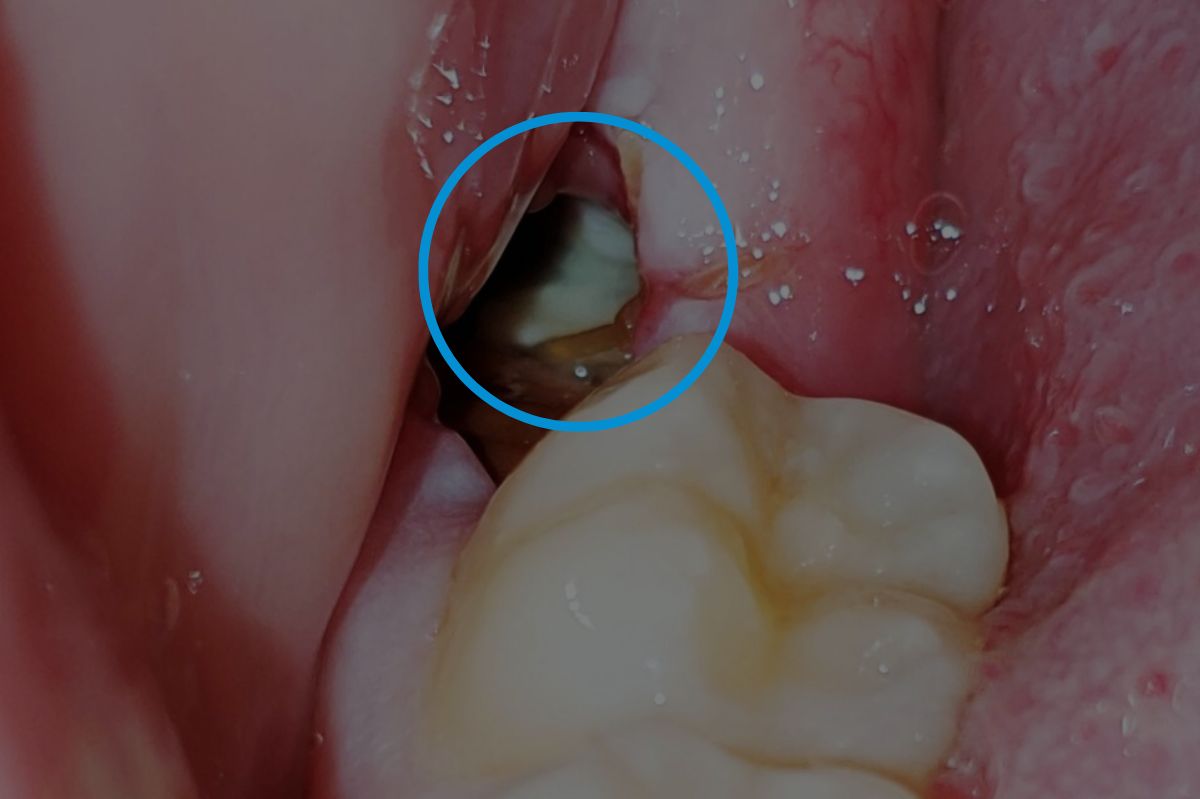

Dry Sockets

- A common issue where the blood clot becomes dislodged, exposing the bone.

- This leads to a dull ache around the third to fifth day after surgery.

- Treatment involves medicated dressings for pain relief and may require multiple visits to replace the dressing.